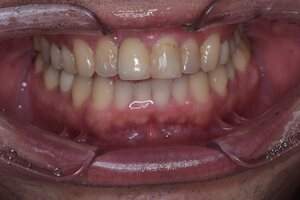

インプラント治療の症例1

症例写真-1

- Befor

- After

| 年齢 | 50代・男性 |

|---|---|

| 主訴 | 右下歯が疼く |

| 治療内容 | ・右下6番インプラント ※1:FGG(遊離歯肉移植術)とは、足りない歯ぐきを上顎から上皮を切り取り移植する外科手術 |

| 治療費 | 合計:902,000円(税込) ■内訳 |

| 治療期間 | 9ヵ月 |

| 治療方針 | 右下の当該歯は歯根破折により保存不可能と診断しました。歯周疾患も伴っていたため抜歯後に骨吸収※1が大きく起こることが予測できました。チタンメッシュ併用骨再生誘導法(GBR※2)を選択しインプラント埋入と同時に行い自然な歯槽骨のラインを再現しました。またGBRを行う際にインプラント辺縁の付着歯肉の減少が起こる為、遊離歯肉移植術(FGG※3)を行い清掃性を考慮した形態に仕上げました。 ■治療方針の解説 治療した右下の歯をレントゲンで撮影したところ根本の部分に黒く写る箇所があり「根尖性慢性周囲炎※1」と診断。また歯周病も進行していました。 ※1 骨吸収・・・歯槽骨という歯を支える骨がなくなっていくこと |

| 担当者所見 | 主訴の右下だけでなく歯茎の腫れ、発赤があり不良補綴や不良充填など他にも治療箇所が多数ありました。プラークコントロールが不良であった為まずはブラッシング指導を行いセルフケアの重要性を理解していただくところからスタートしました。 右下6番の歯はインプラント治療を行なった結果審美的にも機能的にも患者様の満足を得ることができました。骨造成と歯肉移植も行なった為インプラントを支える十分な歯周組織の獲得ができたと思っております。 |